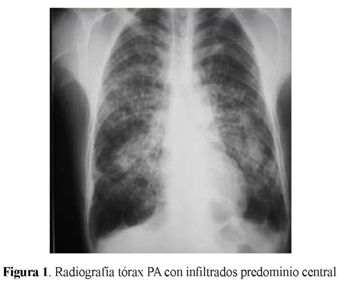

Radiografía de Tórax: infiltrados alveolares e intersticiales bilaterales, parahiliares, atrapamiento aéreo (figura 1)

La radiografía de tórax presenta lesiones intersticiales y en ocasiones alveolares, centrales, bilaterales con áreas hiperlucidas en las bases. La tomografía de alta resolución presenta nódulos, opacidades en vidrio esmerilado, patrón en árbol de gemación, lesiones acinares, bandas parenquimatosas, engrasamiento intersticial peribroncovascular, cavernas, patrón reticular, bulas y bronquiectasias por tracción. Esta forma clásica se presentó en nuestro caso, pero posiblemente asociado a enfermedad pulmonar obstructiva crónica EPOC. La resolución dejó fibrosis pulmonar (5).